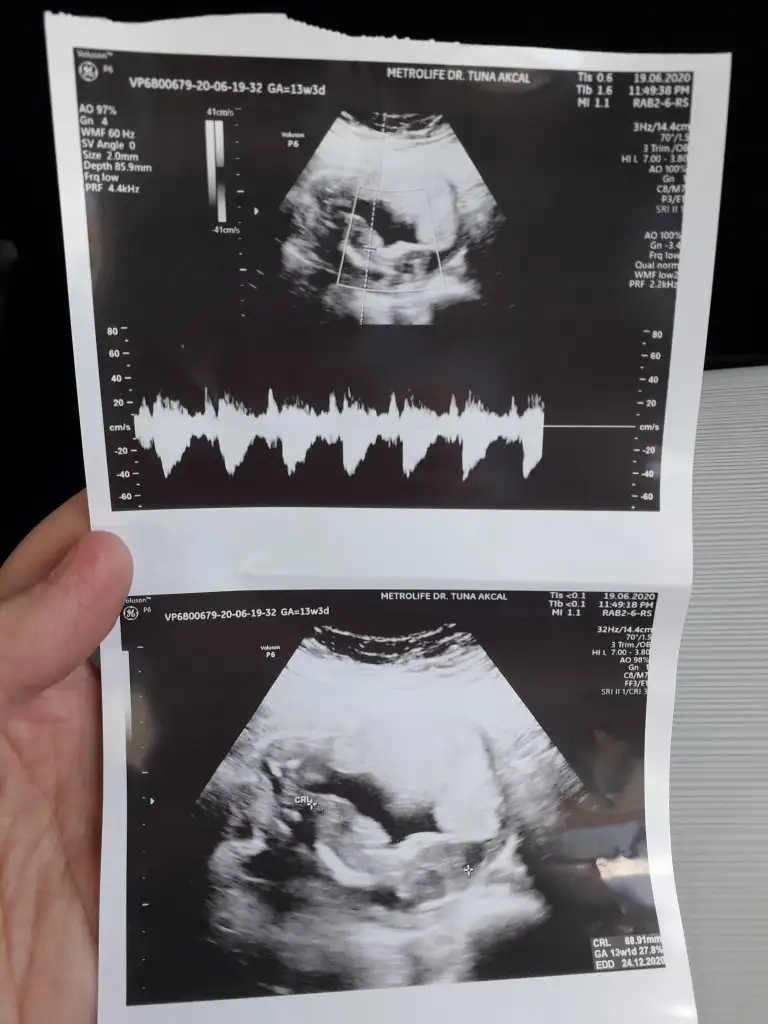

Çok net değil canım bir tahmin edicem olursam kız sankiikra meyra biz tahmin icin haziriz canim minnagim 13+3 doktorumuz kesin olmamakla birlikte bi tahminde bulundu

Yani hiç net değil usg ama yinede belli olmaz daha erken dr kesin dediği zamanı bekleBaska usg yok canim doktor erkege benziyor gibi dedi kesin bisey demedi,, aslinda bacak arasini gosteren bi ani vardi dr onu yakalayamamis cekerkenkese tahminin tuttu ozaman erkek demistin

Erkek gibi sanki 13 hafta usg de paylaşınMerhaba 11+0 günlük usg yorum yapabilir misiniz

Doktorumuz kıza benzetti bakalım hayırlısı öğrenince pylaşırım☺ Birkaç usg daha var onları da ekliyorumErkek gibi sanki 13 hafta usg de paylaşın

Net değil 12-13 hafta olursa paylaşınDoktorumuz kıza benzetti bakalım hayırlısı öğrenince pylaşırım☺ Birkaç usg daha var onları da ekliyorum